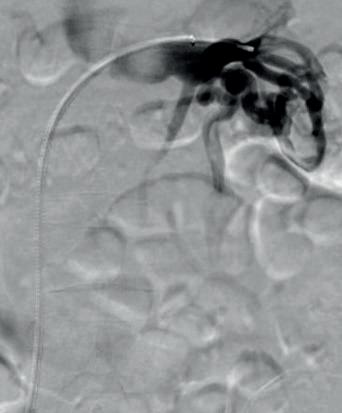

The focus of their study was to establish the role of IR in the management of potentially lifethreatening postpancreatectomy complications such as PPH, thus preventing re-exploration. To do so, Kulkarni and colleagues enrolled 758 patients who underwent pancreatic surgery between January 2014 and December 2019. All patients who developed post-surgical complications within 90 days of primary hospitalisation were included. Complications were classified according to the International Study Group of Pancreatic Surgery (ISGPS).

The types of surgery included in the study were pancreatectomy (4%), pancreaticoduodenectomy (73.8%), enucleation (1%), pancreatectomy and vein resection (4.85%), and multivisceral pancreatic surgery (16.5%). Of the 758 patients included, 206 (27.2%) developed post-surgical complications. Of these, 46 patients (6%) experienced PPH, with 30 patients (3.96%) requiring intervention; 13 patients (43.3%) underwent angioembolization, of whom five (38.46%) died due to causes unrelated to PPH, while 17 patients (56.7%) underwent surgical reexploration.

Elsewhere in their results, the researchers observed intra-abdominal fluid collections in 173 (22.8%) patients, with 147 (85%) undergoing image-guided interventions and 23 (13.3%) undergoing surgical re-exploration. The 90-day mortality rate after percutaneous image-guided intervention was 6.12% and after primary surgical re-exploration was 21.7%.

Among other results, the authors identified that biliary complications occurred in 31 patients (4%), of which 18 (58%) underwent image-guided intervention and 11 (35.5%) underwent surgical re-exploration. The 90-day mortality rates were 27.78% and 35.5% in the IR and surgical groups, respectively. Further,

the incidence of pancreatic fistula was observed in 20% of patients, 91.8% of whom were prevented from undergoing surgical re-exploration by use of IR management. The 90-day mortality rate in patients who underwent percutaneous drainage was 2.7% and 30.3% in those who underwent primary surgical re-exploration.

“Image-guided interventions successfully prevented re-exploration in 61.5% of PPH cases, 88.9% of biliary complications, and 99.3% of intra-abdominal fluid collections,” state Kulkarni et al, emphasising the “pivotal role” IR plays in managing post-surgical complications.

“IR provides a minimally invasive alternative to surgical re-exploration, reducing recovery time and preventing morbidity associated with re-exploration,” say the authors. They highlight that “early recognition and prompt intervention” are key in patients with PPH, biliary leak and portal vein thrombosis, as these are conditions associated with high mortality and morbidity rates. However, in cases where surgical re-exploration is required, this is “often due to complications which are beyond the scope of percutaneous management”, Kulkarni et al point out.